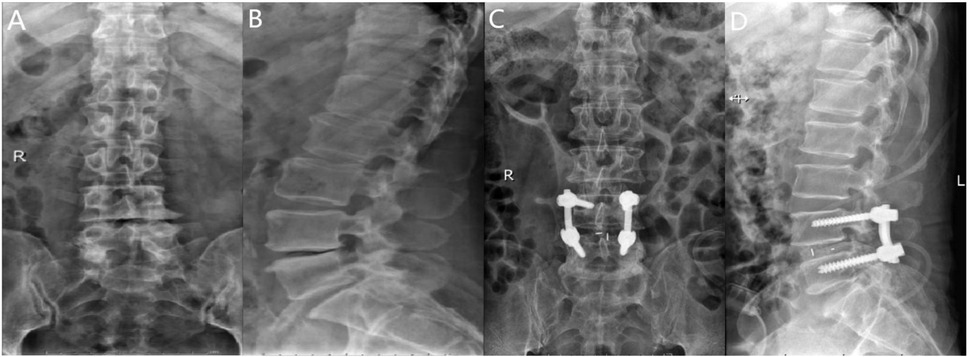

Following general anesthesia, the patient is positioned prone with the abdomen suspended, and a posterior midline incision is made. The paraspinal muscles and soft tissues are dissected bilaterally along the spinous process. Under fluoroscopic guidance, four short-tail universal pedicle screws are inserted into the targeted vertebrae. The spinous process and part of the lamina of the superior vertebra at the diseased intervertebral space are removed, along with the ligamentum flavum. The inner edge of the superior articular process of the inferior vertebra is also removed to complete the decompression. During the procedure, the nerve roots and dura mater are gently retracted medially to allow complete removal of the intervertebral disc and cartilage endplate, exposing the bony endplate. Autologous bone particles are grafted into the intervertebral space to promote bone fusion. Subsequently, an appropriately sized intervertebral fusion device is inserted, and a pre-cut and pre-bent titanium alloy rod is placed and fixed with compression. Postoperatively, the area is carefully checked for active bleeding, and a drainage tube is placed. The incision is closed in layers, and a sterile dressing is applied (Figure 4).

Figure 4. (A) Preoperative anteroposterior radiograph of the lumbar spine; (B) preoperative lateral radiograph of the lumbar spine; (C) postoperative lateral radiograph showing spinal instrumentation; (D) postoperative anteroposterior radiograph showing spinal instrumentation.